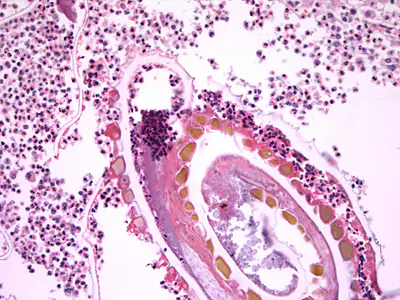

A 61- year-old man presented in 2015 with abdominal pain and was found to have a perforated sigmoid colon. Initial course notable for intra-abdominal collection, associated with the perforation, which was drained. Surgical procedures included sigmoid resection and diverting colostomy. A biopsied specimen revealed cancer and appropriate chemotherapy was administered for 7 months. No reported travel to rural areas or exposure to farm animals and only travel history outside the U.S. was to Canada and the Bahamas on a cruise 25 years ago. The patient has not eaten beef or pork for about 7 years, aside from a 2 month period in 2015 (while undergoing the cancer treatment). As an outpatient he was having carcinoembryonic antigen (CEA) levels monitored, and a recent increase prompted a positron emission tomography (PET) scan that revealed a liver lesion. He was admitted for a right liver lobe resection and a small incidental capsule nodule was noticed, removed and sent to pathology. Previous laboratory results included no evidence of eosinophilia. Figures A–F show what was observed on a hematoxylin and eosin stained section. Figures B and C were captured at 200x magnification; Figures D–F at 400x. What is your diagnosis? Based on what criteria?

Figure B